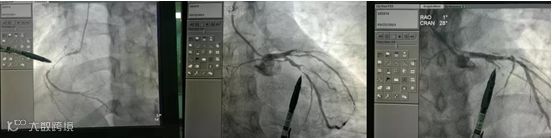

由于长期吸烟,他的三支血管已“面目全非”,为预防术后发生急性心衰,医生还为他植入了IABP泵辅助治疗。